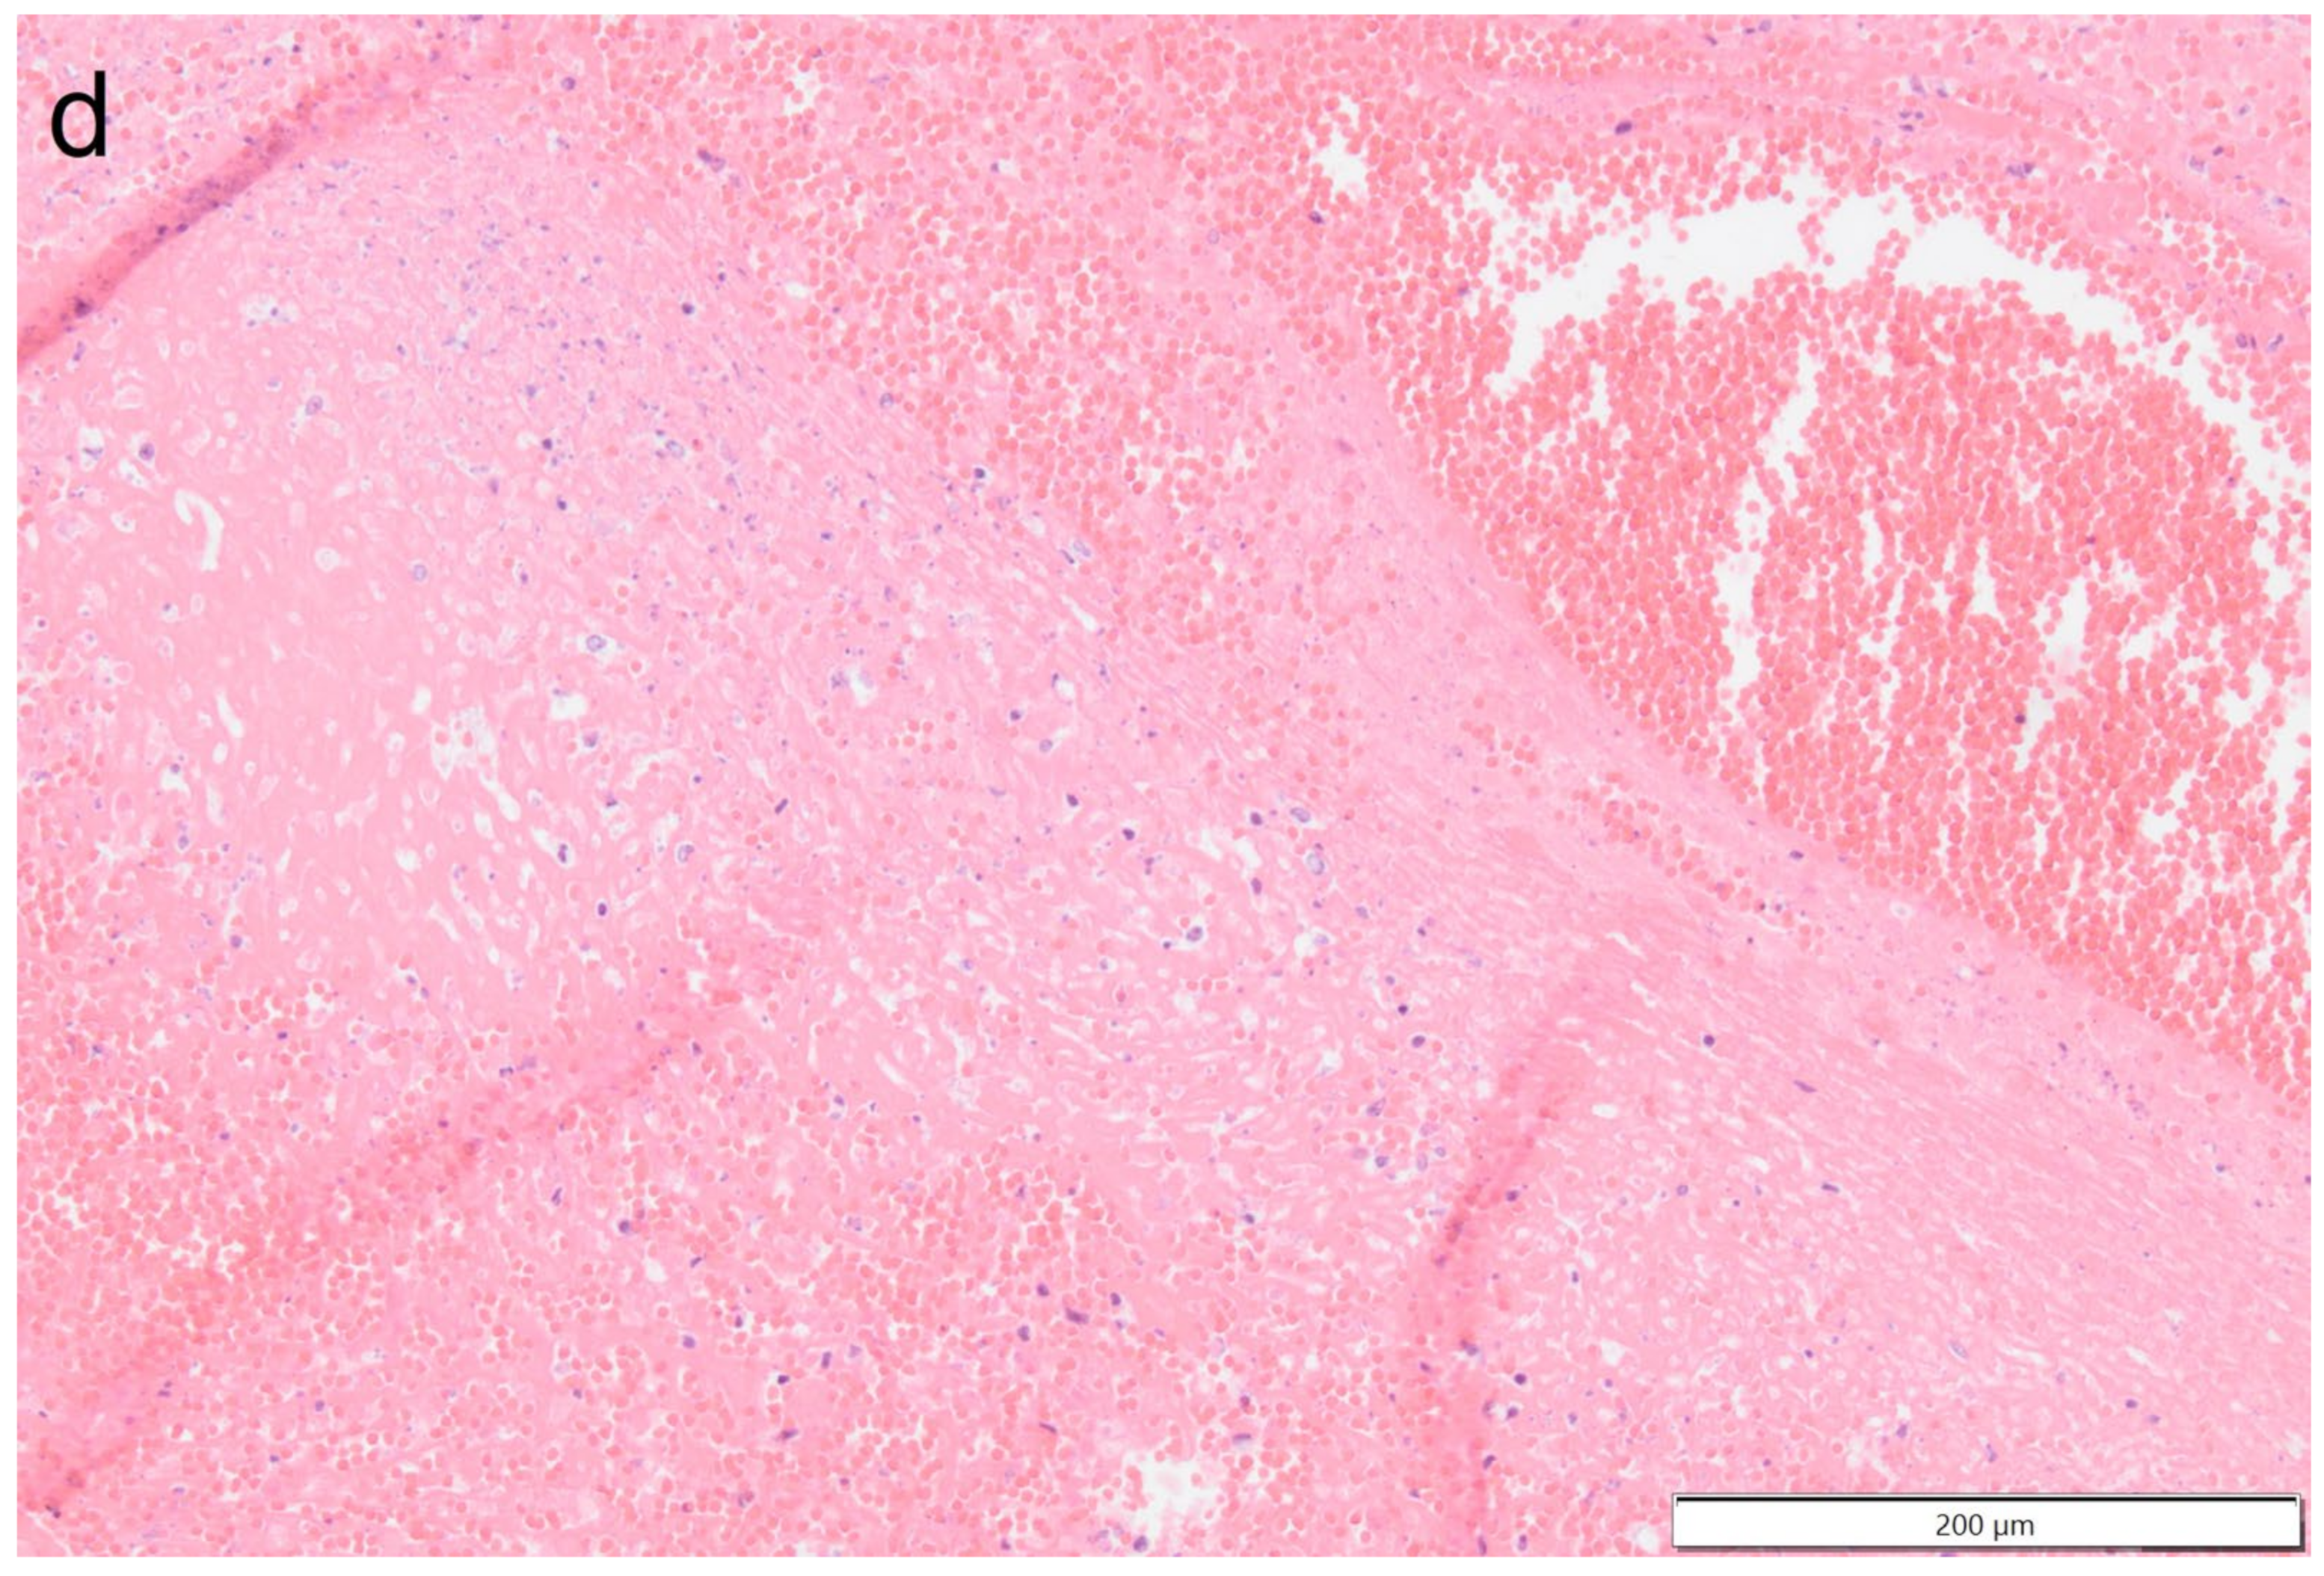

Figure 9.

Photomicrograph overview of the attachment site of the chronic thrombus to the endocardium of the right ventricle. Hematoxylin & Eosin staining, 2× magnification. The insets are shown and described in larger magnification in Figure 10.

Figure 10.

Photomicrographs show the attachment site of the chronic thrombus to the endocardium of the right ventricle. Hematoxylin & Eosin staining, 10× magnification. Marked mononuclear inflammation expands the myocardium (a) and (sub)endocardium at the site of thrombus attachment (b), which is further expanded by vascularized connective tissue confluent with the periphery of the thrombus (organization, (c)). The majority of the thrombus consists of a fibrino-necrotic core with islands of erythrocytes (d).